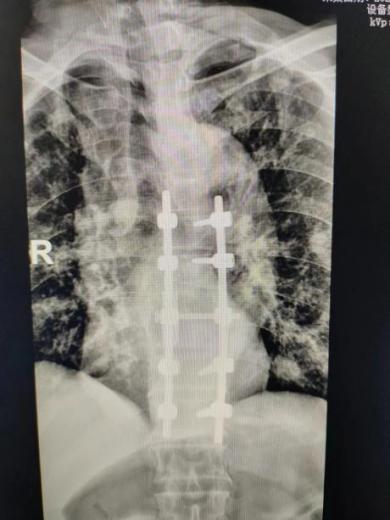

科室团队在经过精细讨论,通过MDT多学科会诊后,充分评估了该患手术风险及预后,术前给予抗结核药物治疗,同时为其在全麻下行胸椎后路经椎弓根环形减压病灶清除椎间融合内固定手术。术后患者双下肢肌力恢复至1-2级,出院前已能拔出尿管,自主排尿、排便。患者及家属对手术效果极其满意。

随着后路手术关键技术的不断改良,单纯后入路手术可通过椎弓根清除病灶,对神经脊髓充分减压,通过脊柱三柱结构重建对脊柱行三维矫形,利用钉棒内固定术达到病椎的稳定固定,其优点在于手术创伤小,尽可能避免单纯前路手术对脏器或者血管的损伤,有效降低内固定物失败等并发症的出现。